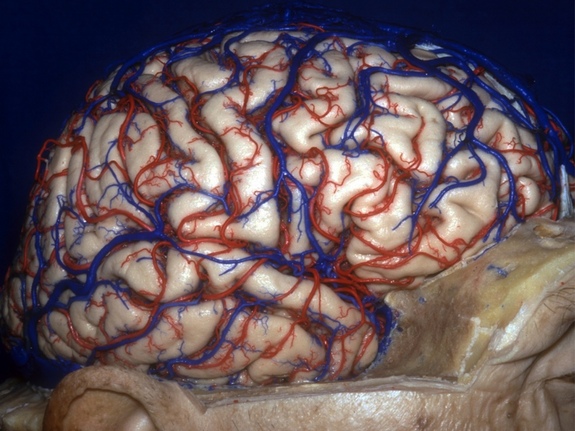

Estas imágenes son parte de una colección de anatomía del cerebro humano hechas por el Dr. Albert Rhoton (November 18, 1932 – February 21, 2016) un neurocirujano y profesor de la Universidad de Florida, las imágenes permiten a los cirujanos ver las estructuras cerebrales delicadas en ángulos precisos.

Con tintes azules y rojos brillantes los vasos sanguíneos son visibles con mayor facilidad, por lo que los cirujanos pueden planificar mejor los enfoques quirúrgicos delicados. Explora la geografía del cerebro humano a través de esta colección de imágenes del Dr. Rhoton disponibles en iTunes.

Mirando lateralmente, esta imagen muestra al hemisferio cerebral derecho. A pesar de las afirmaciones hechas por la psicología popular, el hemisferio derecho no es especialmente creativo, ni el cerebro izquierdo inherentemente más lógico. Un dato curioso es que la información sensorial de cada lado del cuerpo, viaja al lado opuesto del cerebro.